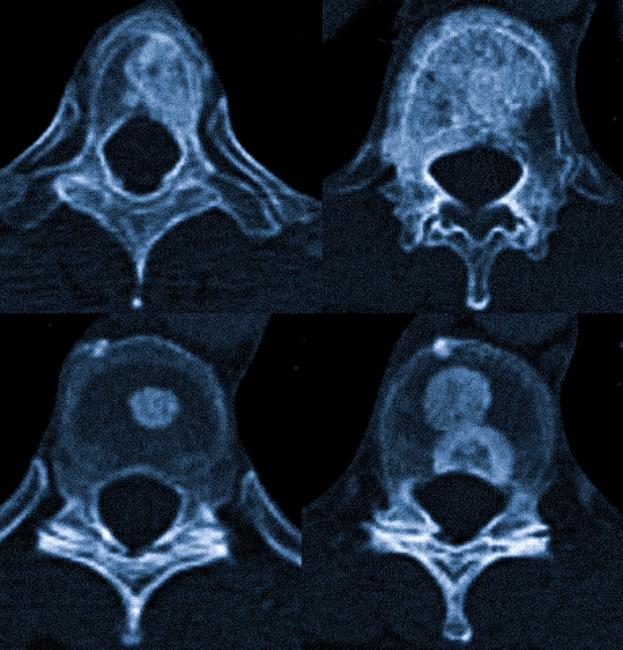

Видит ли КТ метастазы в костях

Врач, просматривая компьютерные томограммы, способен выявить костные метастазы, затронувшие кортикальный слой (с визуализацией поражения губчатого вещества лучше справляется МРТ). КТ позволяет определить тип, локализацию, размеры и распространенность очагов деструкции или патологического склероза.

Метастазы в костях на КТ как выглядят

Метастазы, выявляемые с помощью КТ, можно разделить на три группы:

- остеобластные (склеротические) — участки с повышенной костной плотностью, визуально выглядящие как “белые” пятна;

- остеокластические (остеолитические, деструктивные) — “черные” очаги с пониженной плотностью по сравнению с окружающей тканью, угрожающие возникновением патологических переломов;

- смешанные, совмещающие оба типа изменений структуры кости.

При множественной миеломе плоские кости получают “прожжённый” вид, что может имитировать диффузные остеокластические метастазы. Предпочтительные локализации деструктивных очагов при этом заболевании — череп, таз и ребра.

В дифференциальной диагностике остеолитических метастазов позвоночника рассматриваются как единичные, так и распространенные гемангиомы. Данная патология чаще встречается в грудной области и реже — в поясничной. КТ демонстрирует сохраненные костные балки (симптом “польского горошка”) и позволяет оценить подозрительные очаги по шкале Хаунсфилда. Для метастатического процесса характерна мягкотканная плотность, тогда как гемангиома имеет жировую плотность.